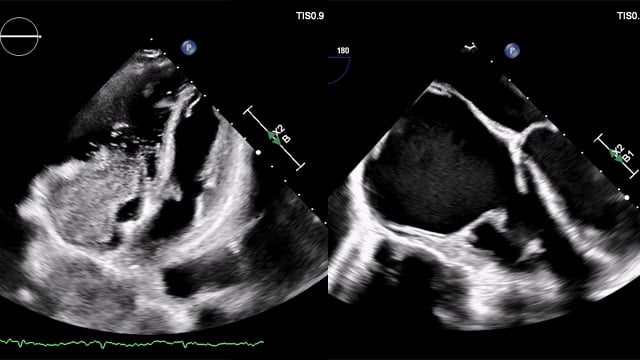

Severe MR in a high-risk patient with a suboptimal anatomy for M-TEER: what other options can we find?

Multimodality imaging reveals fibro-calcific leaflet disease, restricted motion, and a short posterior leaflet, making him a suboptimal candidate for M-TEER and prompting consideration of transcatheter mitral valve replacement. How would you treat?